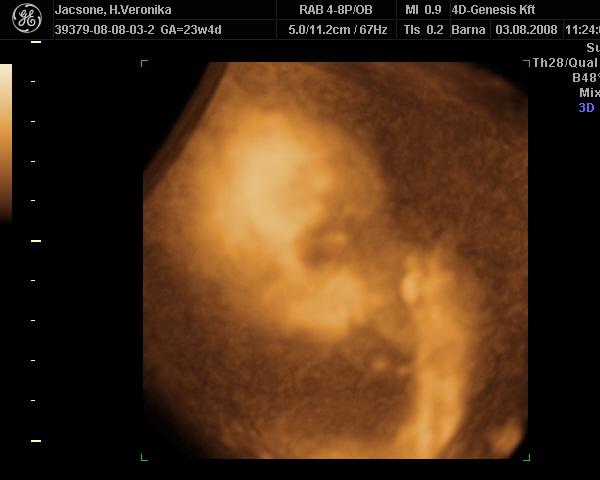

Gyönyörű ez a kis Négyeskétek!

Tényleg írtó éles a kép

Megérte a többszöri visszamenést!